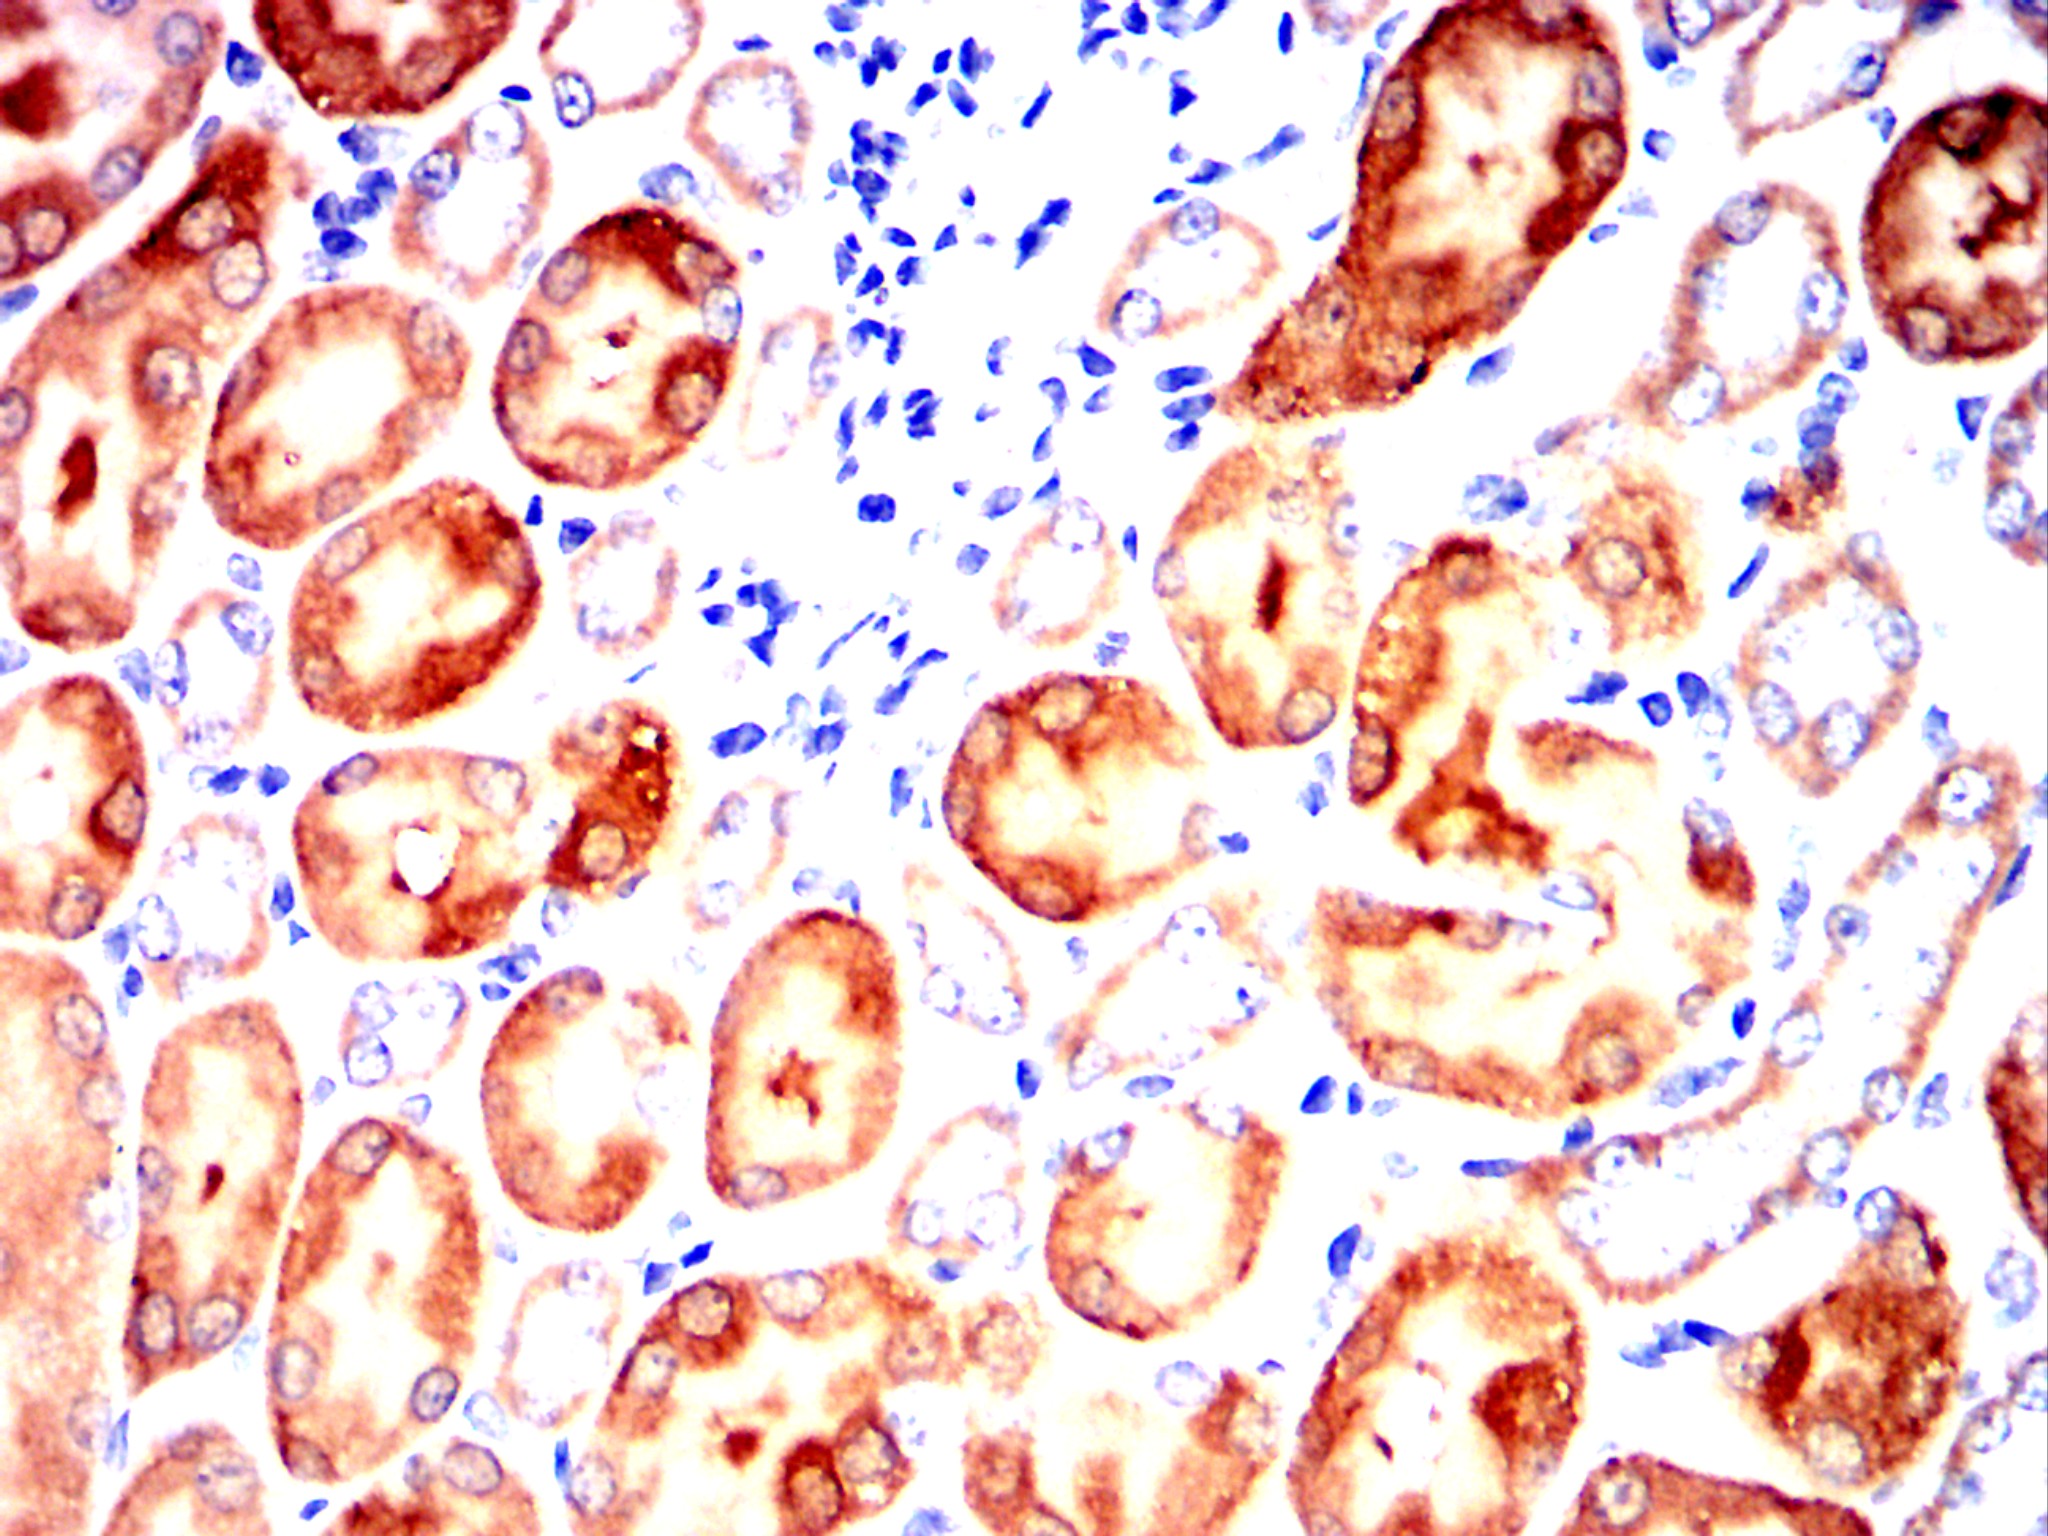

Immunohistochemical analysis of paraffin-embedded human lung cancer tissues using SST mouse mAb with DAB staining.

Immunohistochemical analysis of paraffin-embedded Rat kidney using SST mouse mAb with DAB staining.